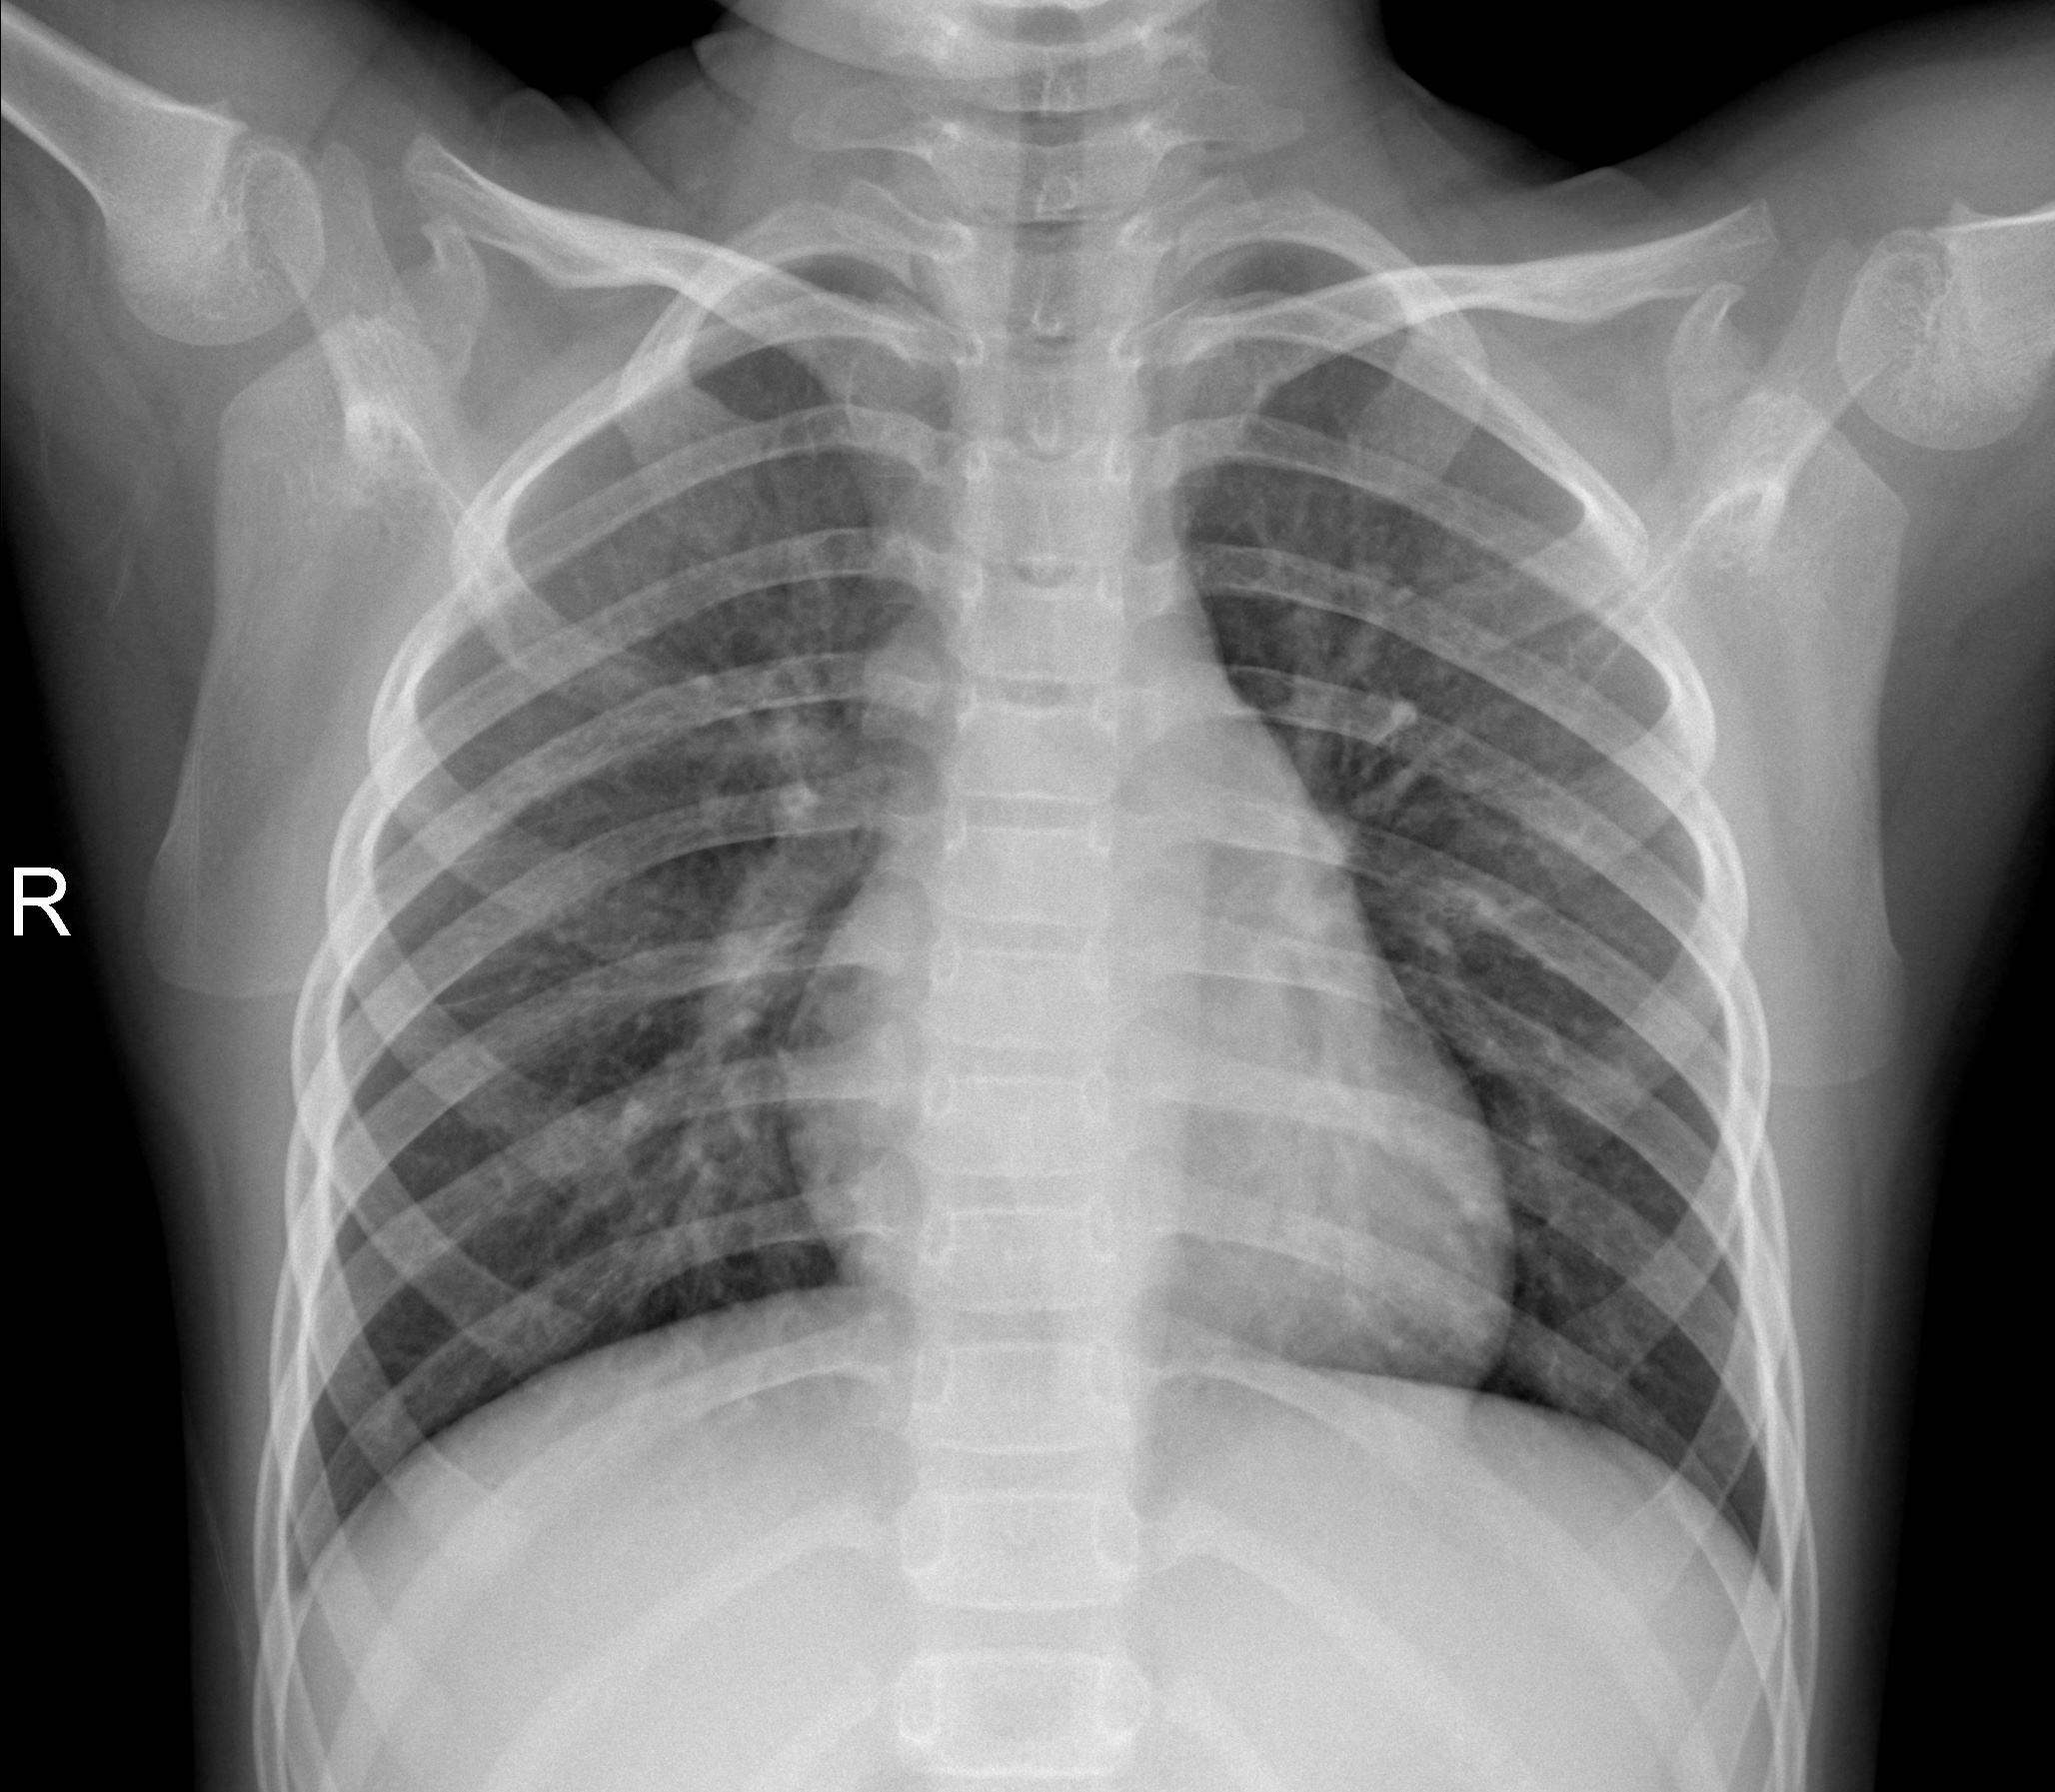

Normal

Normal